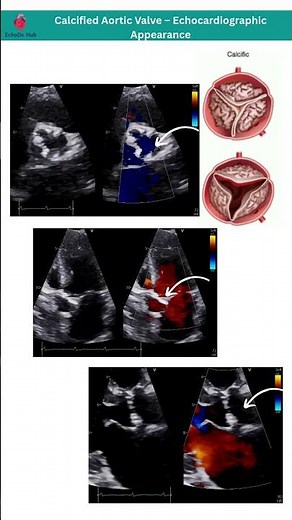

Echo - Aortic

in Echo - Stenosis Aortic

Calcified Valve - USMLE Aortic

Valve Calcification - Coronary

of the Aortic Valve - Mild Aortic

Calcification - Severe Aortic Calcification

Ehco